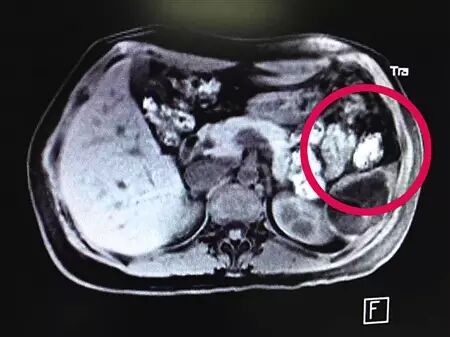

B超图上的圆圈处为胎儿所处位置

6月中旬,家住巴南区的王婷(化名)经血液检查发现自己怀孕了,眼看着孕期已经3个月,但B超检查却怎么也找不到子宫里的胎儿。最终,王婷接受了肝胆胰脾肾超声检查,医生在脾脏里发现了发育中的胎儿。7月15日,第三军医大学西南医院为王婷终止妊娠并切下部分脾脏。该院专家称是第一次遇到这样的病例,而类似的“脾脏妊娠”在世界上都十分罕见。

脾脏部位发现活生生胎儿

7月12日,王婷前往另一家医院做B超检查,医生还是没有在她的子宫和盆腔内发现胎儿。按常理推断,如果王婷确实怀孕,则孕期已有3个月了。王婷说,医生怀疑胎儿掉到了其他部位,因此建议她检查一下其他器官。王婷同意了,并做了肝胆胰脾肾超声检查。最后,医生在王婷的脾脏部位发现了一个活生生的胎儿。

15日上午,王婷的脾脏部位开始明显疼痛,因担心胎儿生长过快会破坏脾脏,医生决定下午立即手术。经过2个半小时的手术,王婷的下半部脾脏连同胎儿被切除。“胎儿已经和2~3个月的胎儿差不多大小了,还长出了头、脸、鼻、眼睛、四肢等。”西南医院肝胆科的李建伟副教授说。